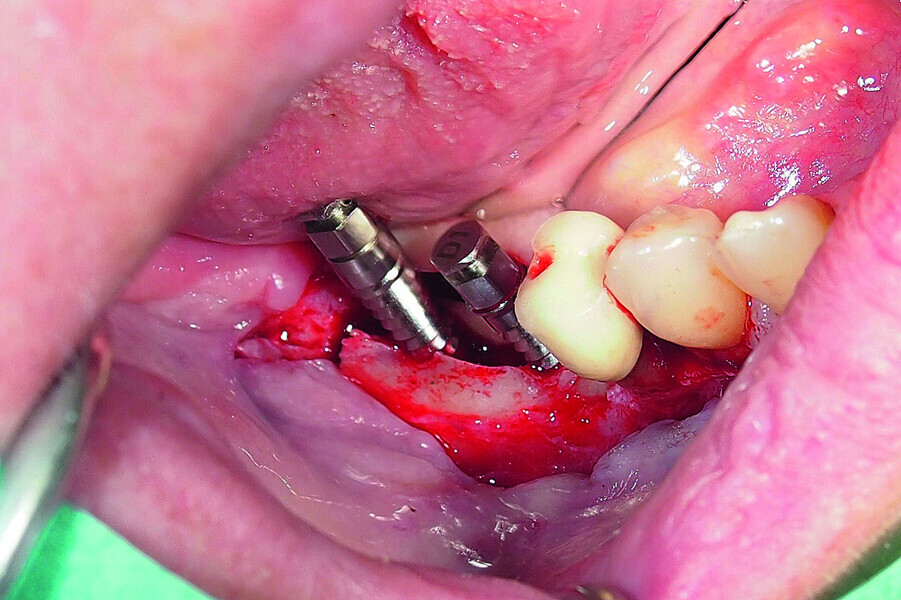

Fig. 18: Placement of two GC Aadva Standard implants with regard to the future restorative margins.

Fig. 19: Bone defect filled with xenograft and covered with an absorbable collagenous membrane.